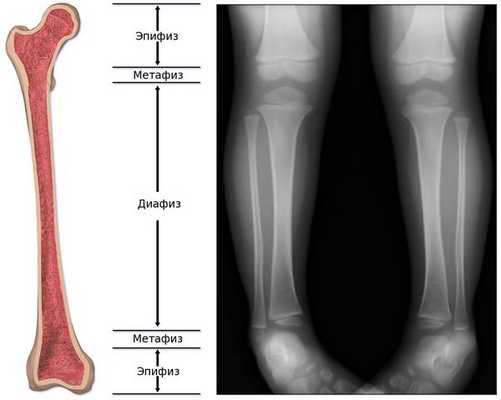

Статистическая обработка материала осуществлялась стандартными методами. Были получены следующие результаты. Теоретической основой работы послужили широко известные данные о физико-химических особенностях метаболизма фосфатных комплексов, меченных Тс-99m РФП [6]. Данный индикатор интенсивно диффундирует из кровеносного русла и накапливается в остеобластах, а также в матрице вновь формирующейся остеоидной ткани в мета- и эпифизарных участках трубчатых костей, характеризующихся высоким уровнем васкуляризации и активности костного мозга [2, 3, 8].

Обычно считается, что для того, чтобы увидеть состояние костей, лучше прибегнуть не к ультразвуковой, а к рентгенологической диагностике . На рентгенограмме ясно видны укорочение и искривление длинных трубчатых костей, а также просветление "языков", которые выступают из метафиза в сторону диафиза, являющееся наиболее специфической диагностической картиной при гипофосфатазии. [24]

При гипофосфатазии происходит относительно хорошее окостенение средней части диафиза (тела) длинных трубчатых костей, однако к периферии костей оссификация постепенно ухудшается, и на участках метафиза видна только поверхность костей. Поэтому на рентгенограмме это визуализируется как просветление "языков" пониженной плотности. [13]